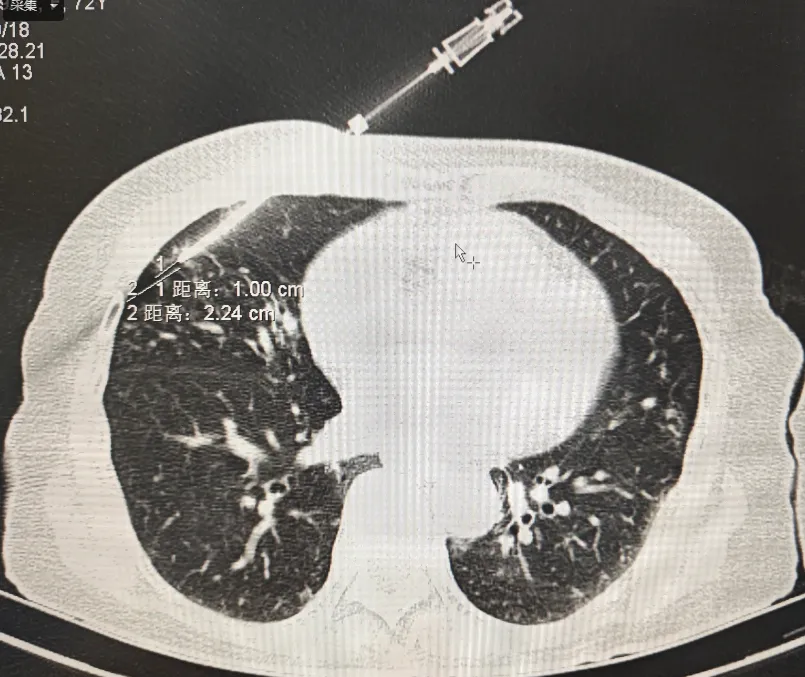

此次手术由肺病科与放射科团队联合开展,在CT的精确定位下,医疗团队成功获取病变组织样本,病检结果为肉芽肿。患者术中生命体征平稳,术后复查未出现气胸、出血等并发症,既为患者明确了肺结节的性质,也打开了余婆婆和家属的心结。

经皮穿刺肺活检术是借助先进的CT扫描技术,实现病灶的三维重建和精确定位,确保穿刺针能够准确到达目标区域,并通过皮肤穿刺直接获取病变组织进行病理学检查的一种微创诊断方法。该技术具有创伤小、痛苦少、并发症低、恢复快等优势。